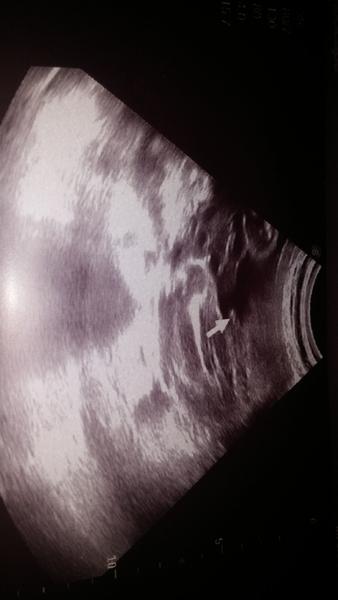

@estrellita uz jsem je tu vkladala prvni foto pred 2 lety jasny kluk..druhe fito nynejsi tehotenstvi ze 16tt a treti foto z 24tt.